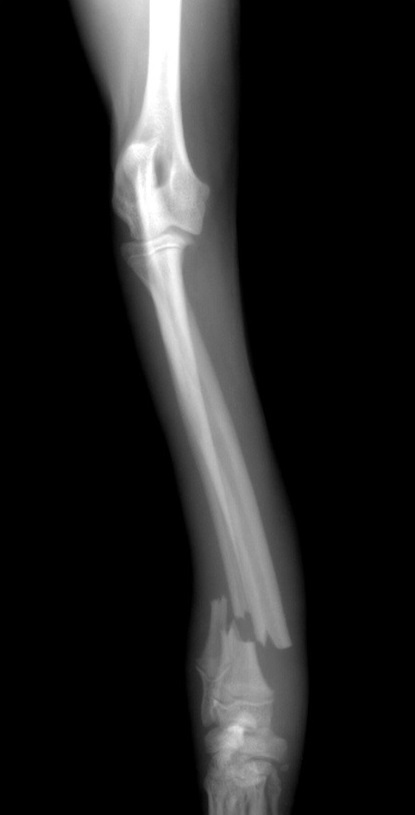

骨折の治療は手術による整復が第一選択となり、(写真)のような金属プレートをインプラントしたり、骨に金属ピンを刺して固定する創外固定などが主な固定方法として挙げられます。